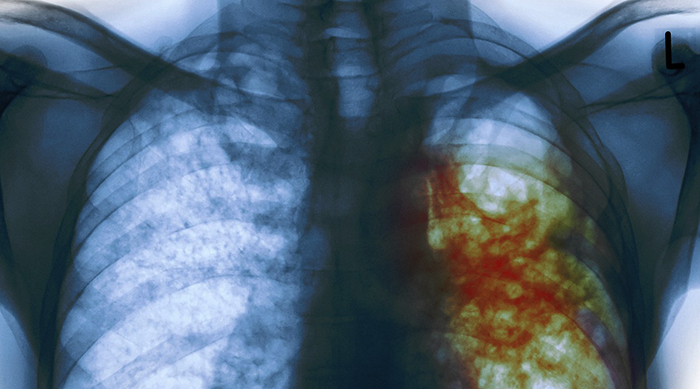

К сожалению, диагностировать заболевание не всегда возможно сразу, поскольку в начальной стадии оно не проявляет явных симптомов и постепенно развивается в легких, пока человек не подозревает о его наличии.

- Неприятные ощущения в области груди.

- Дискомфорт при кашле.

- Постоянное сухое кашление.